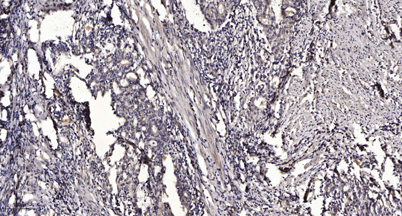

Product name: Shb (phospho Tyr246) rabbit pAb

Dilutions: WB 1:500-2000;IHC-p 1:50-300

Immunogen: Synthesized phospho-peptide around the phosphorylation site of human Shb (phospho Tyr246)